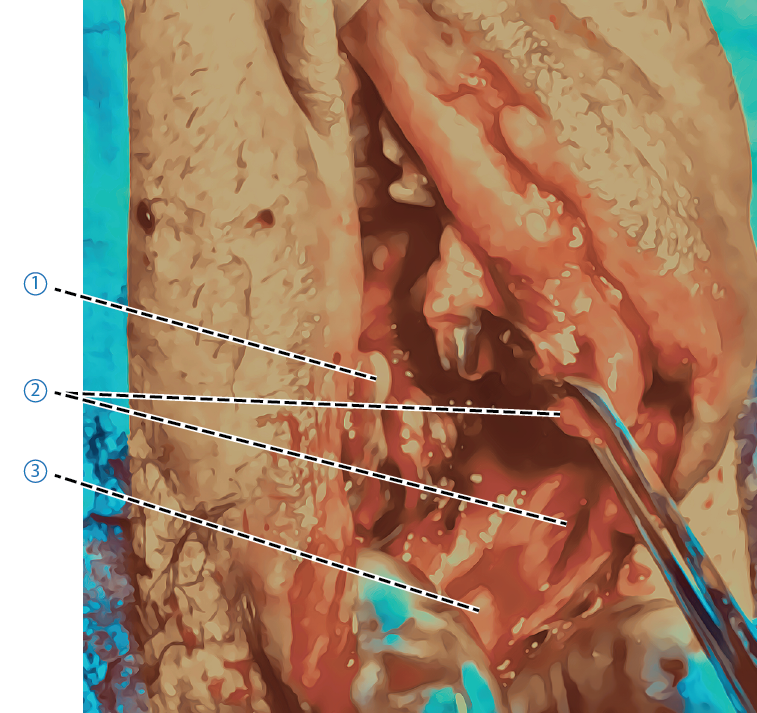

Adaptera muskelfästet för den ytliga delen av transversus perinei i medellinjen närmast den externa sfinktern. Ofta följer m bulbocavernosus med i denna sutur, om den inte följt med i suturen kan den vid behov sutureras ner mot m transversus perinei. Nedan visas bild på m bulbocavernosus som fäster mot ytliga delen av transversus perinei och därmed inte behövde sutureras (Figur A). Figur B visar m bulbocavernosus som släppt från m transversus perinei superficialis lateralt om mittlinjen.- Ytliga muskelfästet för M Transversus Perinei

- Hymen

- Delat muskelfäste för m. Bulbocavernosus

- Ytliga muskelfästet för M Transversus Perinei

Figur B.